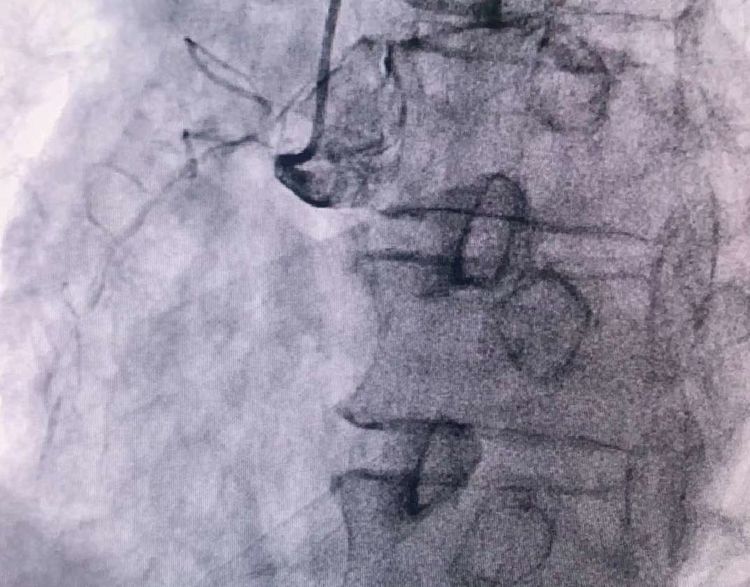

患者71岁高龄,外地医保患者。无高血压、糖尿病、吸烟病史。突发胸痛2小时急诊来院,病情就是命令。接到电话,立即启动我院的胸痛绿色通道,绕行CCU直达导管室。二线手术医生李妮妮责任总和冯韩章责任总,立即上台,给患者行冠脉造影。

患者前降支、右冠100%闭塞,LCX中段60%狭窄。命悬一线,手术台上持续胸痛。和患者家属及时沟通后,决定行PTCA术。血压低至60/40mmHg,在主动脉内球囊反博的支持下紧急行PCI术。轨道很快建立,导丝也及时通过病变血管,噩梦来了,患者发生室颤了。在吴栋梁院长的指挥下,李阳主任和心脏团队的成员共同努力下,除颤、冠脉内溶栓、多个球囊轮流上阵,患者病情平稳了,罪犯血管及时开通,血流恢复三级血流。平安下台,准备择日再处理冠脉情况。